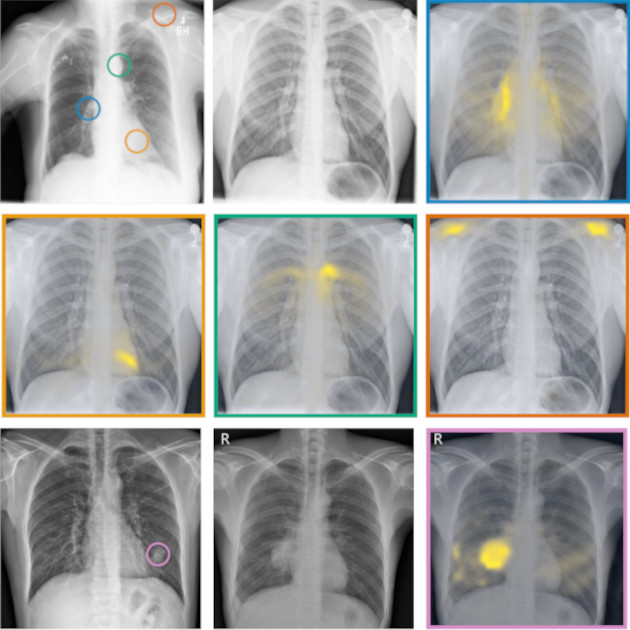

RadEdit: stress-testing biomedical vision models via diffusion image editing

Fernando Pérez-García, Sam Bond-Taylor, Pedro P Sanchez, Boris van Breugel, Daniel C Castro, Harshita Sharma, Valentina Salvatelli, Maria TA Wetscherek, Hannah Richardson, Matthew P Lungren, Aditya Nori, Javier Alvarez-Valle, Ozan Oktay, and Maximilian Ilse

European Conference on Computer Vision (ECCV), 2024

Biomedical imaging datasets are often small and biased, meaning that real-world performance of predictive models can be substantially lower than expected from internal testing. This work proposes using generative image editing to simulate dataset shifts and diagnose failure modes of biomedical vision models; this can be used in advance of deployment to assess readiness, potentially reducing cost and patient harm. Existing editing methods can produce undesirable changes, with spurious correlations learned due to the co-occurrence of disease and treatment interventions, limiting practical applicability. To address this, we train a text-to-image diffusion model on multiple chest X-ray datasets and introduce a new editing method, RadEdit, that uses multiple image masks, if present, to constrain changes and ensure consistency in the edited images, minimising bias. We consider three types of dataset shifts …